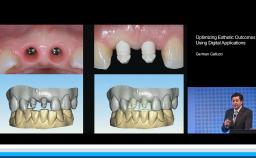

Complications in Regeneration and Reconstruction

This lecture reviews in detail the various defects encountered in clinical practice that may need regenerative procedures for hard and soft tissue augmentation. The presentation is supported with excellent visual aids that illustrate how these defects can be reconstructed for prosthodontically driven implant placement. It also addresses how to prevent complications in regenerative and reconstruction procedures as well as the predominant treatment options to manage these complications. Clinical outcomes are supported by reference to several studies and clinical recommendations from the 4th ITI Consensus Conference.